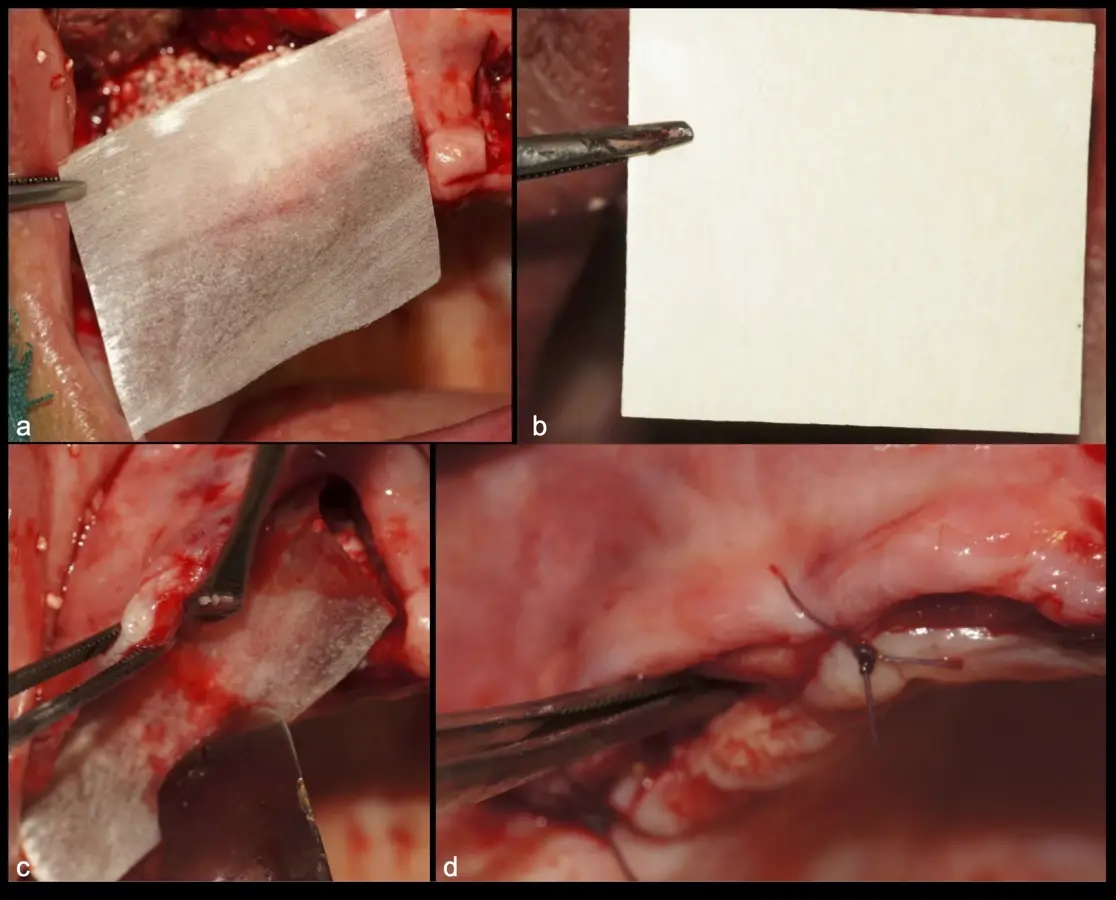

Los casos clínicos que presentamos a continuación muestran claramente las ventajas del piezoeléctrico en diversos procedimientos de terapia ósea regenerativa. En el primer ejemplo, una reconstrucción de reborde con injertos en bloque previo a la planificación de implantes dentales en un caso de edentulismo total superior con una severa reabsorción ósea. En el segundo ejemplo se utilizó esta tecnología para la reconstrucción de lechos para implantes de estructuras óseas con hueso en bloque de origen bovino y posteriormente la colocación de implantes dentales. Los dos casos son parte del capítulo 9 del libro “Cirugía piezoeléctrica: generalidades y aplicaciones clínicas”.